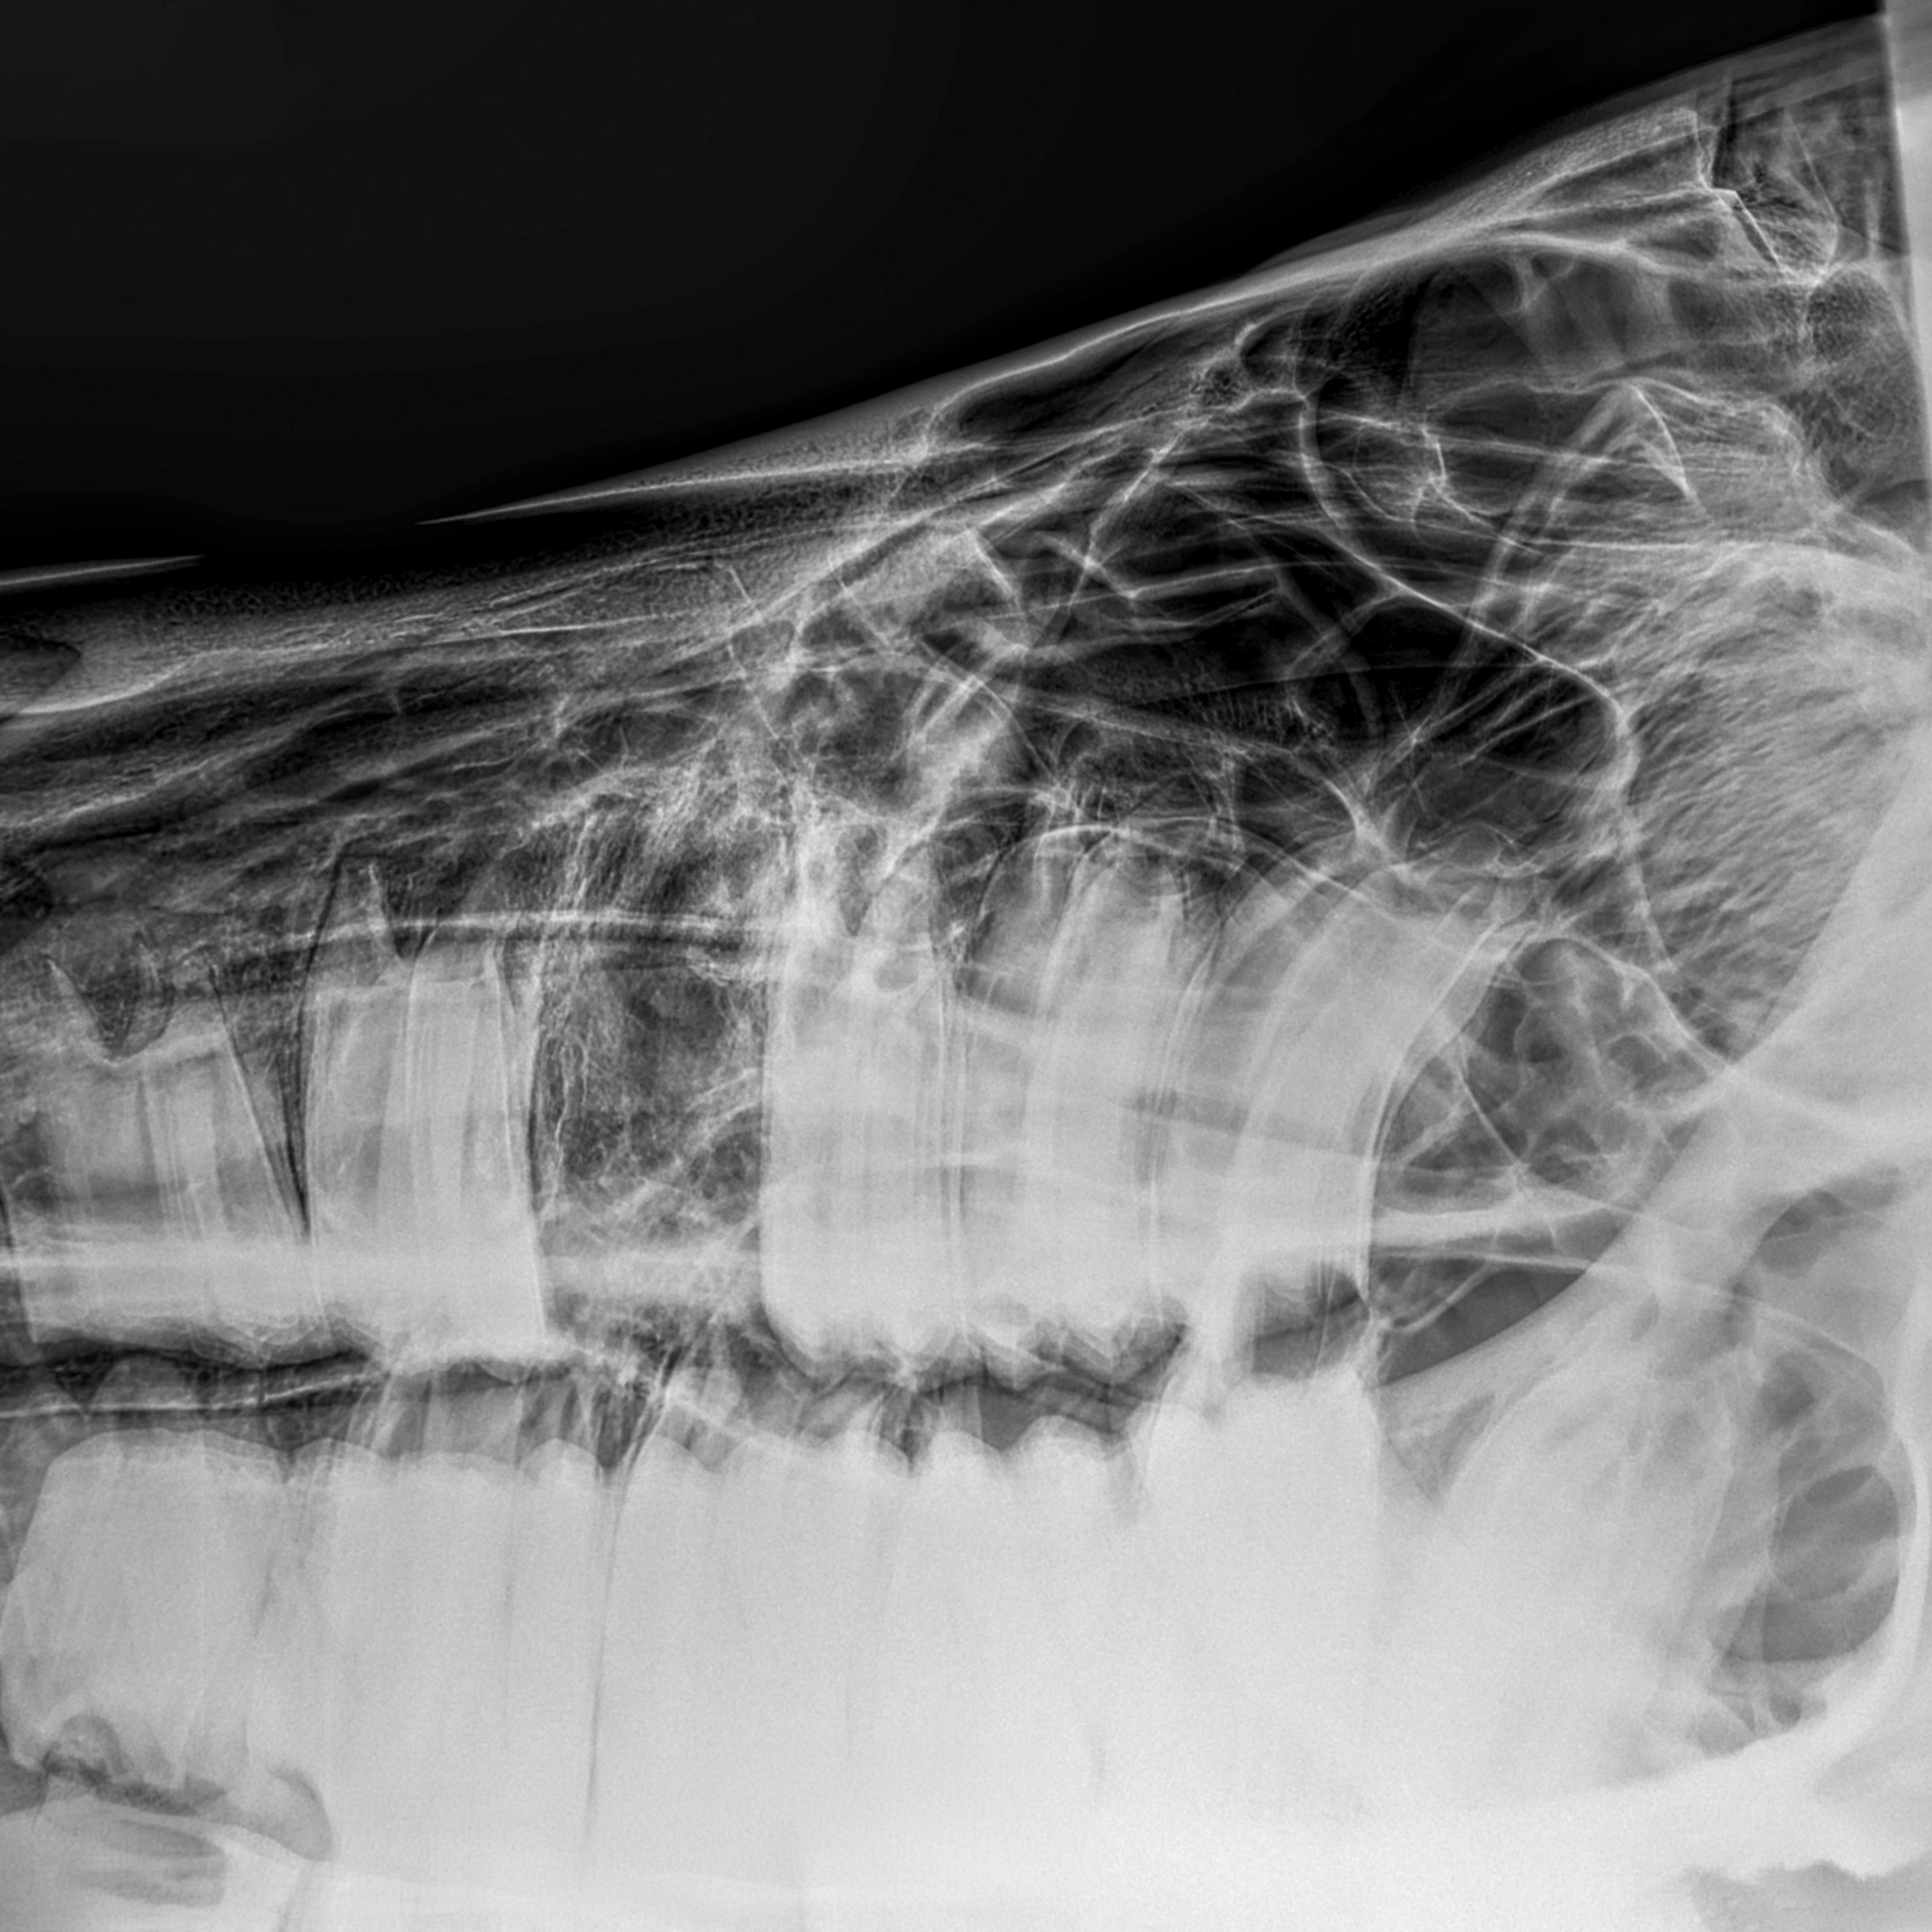

Eine gründliche klinische Untersuchung in Kombination mit moderner Bildgebung ermöglicht eine präzise Beurteilung des betroffenen Zahns sowie der umliegenden Strukturen. So kann die Behandlung sorgfältig geplant und Risiken minimiert werden.